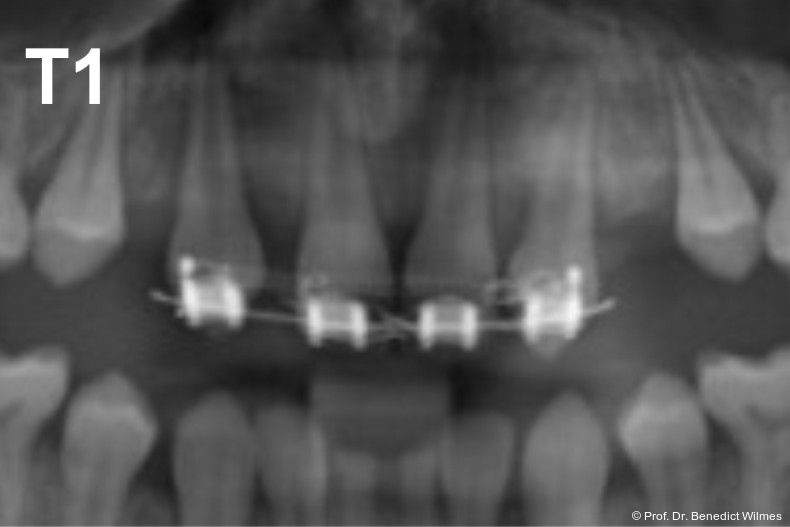

Ein 14-jähriger Patient wurde bei Aplasie der beiden oberen seitlichen Schneidezähne mit dem Ziel der beidseitigen Lückenöffnung kieferorthopädisch therapiert (Abb. 1a+b). Zum Ende der kieferorthopädischen Behandlung wurden zwei Miniimplantate in Regio 2er als temporärer Zahnersatz inseriert (Benefit System, PSM, 2 x 13 mm, Abb. 2a+b). Nach Abdrucknahme wurden Kronen auf den Peek-Abutments modelliert und diese mit Kunststoff auf die Abutments geklebt (Abb. 3a–d). In den Abbildungen 3 und 4 sind die klinischen und röntgenologischen Nachkontrollen innerhalb der nächsten achteinhalb Jahre dokumentiert. Man erkennt einen sowohl in der Höhe als auch in bukkopalatinalen Breite verbleibenden gesunden Knochen ohne Anzeichen einer Atrophie. Im Alter von 23 Jahren wurden die definitiven Implantate ohne die Notwendigkeit einer Augmentation eingesetzt (Abb. 5) und nach Einheilung prothetisch versorgt (Abb. 6a–e und Abb. 7a–c).